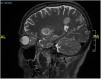

Pruebas complementariasSe realizaron 2 biopsias cutáneas en una placa y un nódulo subcutáneo. El examen histopatológico confirmó una presencia considerable de hifas alargadas y septadas invadiendo la dermis y la epidermis hasta el estrato córneo (fig. 2A). También se observó una extensa necrosis adiposa similar a la paniculitis e hifas en el interior del tejido adiposo (fig. 2B). Antes de la confirmación micológica, el paciente quedó en estado de obnubilación. La TC cerebral de urgencia reveló la presencia de lesiones parenquimatosas compatibles con émbolos sépticos. La resonancia magnética posterior (fig. 3) confirmó estos hallazgos.